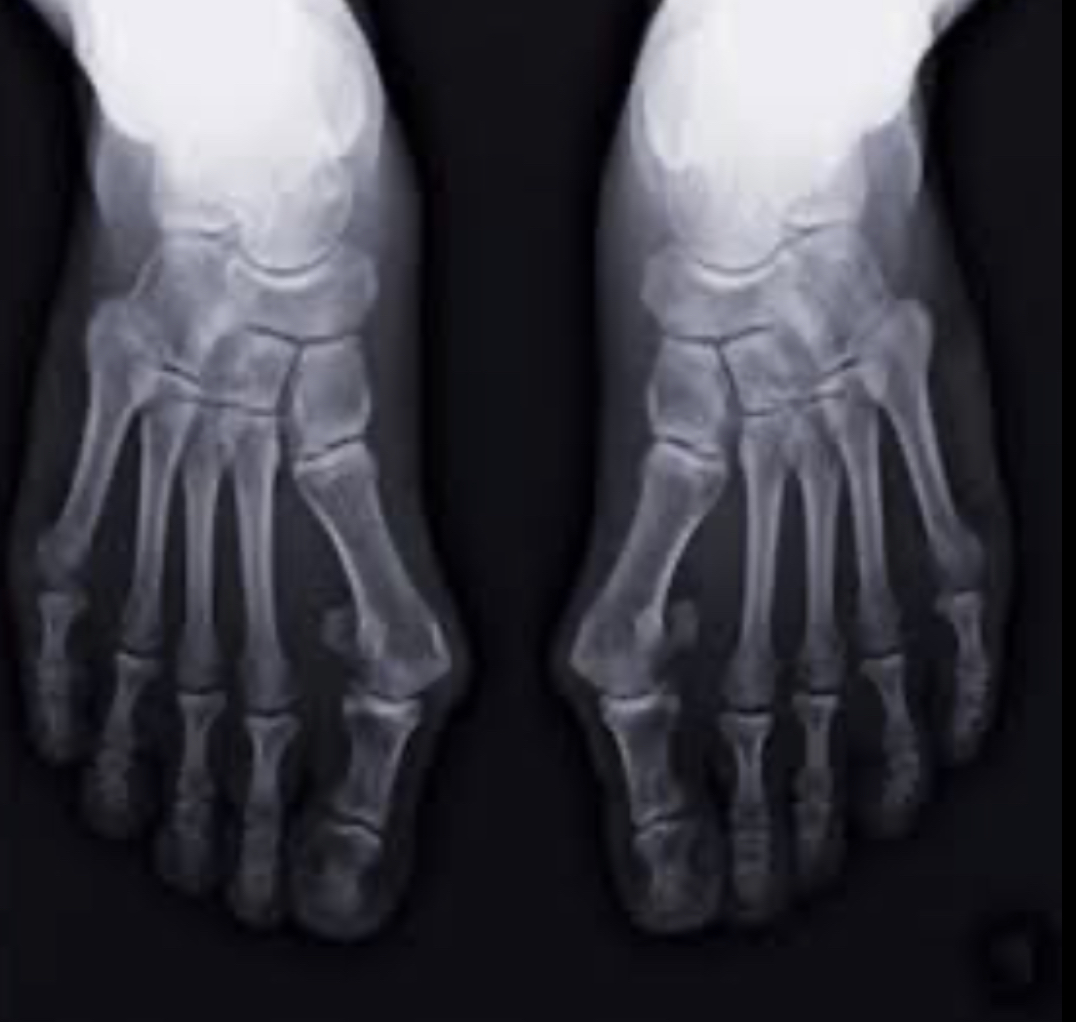

外反母趾の足は

本来の精密な構造の足から崩れた状態にあります

- 正常な骨の並び

- 外反母趾で崩れた骨の並び

足の指は重なり狭くなったかのように見えますが

中足骨(ちゅうそっこつ)という、真ん中の骨の部分は横に広がっているのです。

親指の骨は、中足骨とその先の骨が捻じれた状態にあります。

この状態で体重の1.2倍の衝撃を受けるのです。